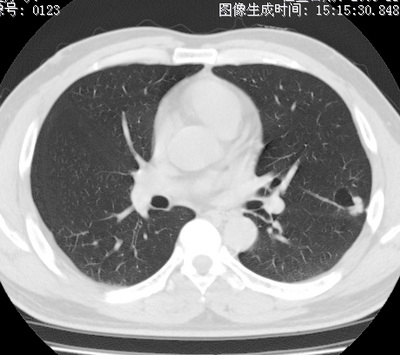

以下是引用zhao_bin2008在2010-1-4 20:15:00的发言:[br]先天性肺囊肿或小的肺隔离症?

以下是引用卜一在2010-1-4 22:09:00的发言:[br]先天性肺囊肿或小的肺隔离症?支持!

以下是引用zsl6918在2010-1-5 5:23:00的发言:[br]良性改变!肺囊肿,先天性支气管闭锁,血管畸形等均有可能。

以下是引用影像之路在2010-1-6 11:10:00的发言:[br]腺癌,最终的病检有些出乎意料之外,术前同志们大多考虑为肺囊肿或小的肺隔离征 [br]回过头来看 小结节呈分叶状,其内侧有一条较粗的静脉供血或许能成为支持诊断腺癌的理由